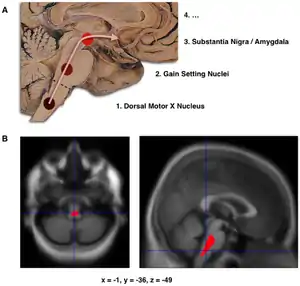

The main pathological characteristics of PD are cell death in the brain's basal ganglia (affecting up to 70% of the dopamine secreting neurons in the substantia nigra pars compacta by the end of life).[70] In Parkinson's disease, alpha-synuclein becomes misfolded and clump together with other alpha-synuclein. Cells are unable to remove these clumps and the alpha synuclein becomes cytotoxic, damaging the cells.[11][77] These clumps can be seen in neurons under a microscope and are called Lewy bodies. Loss of neurons is accompanied by the death of astrocytes (star-shaped glial cells) and a significant increase in the number of microglia (another type of glial cell) in the substantia nigra.[78] Braak staging is a way to explain the progression of the parts of the brain affected by Parkinson's disease. According to this staging, PD starts in the medulla and the olfactory bulb before moving to the substantia nigra pars compacta and the rest of the midbrain/basal foerbrain. Movement symptom onset is associated when the disease begins to affect the substantia nigra pars compacta.[14]

- Schematic initial progression of Lewy body deposits in the first stages of Parkinson's disease, as proposed by Braak and colleagues

- Localization of the area of significant brain volume reduction in initial PD compared with a group of participants without the disease in a neuroimaging study, which concluded that brainstem damage may be the first identifiable stage of PD neuropathology[79]